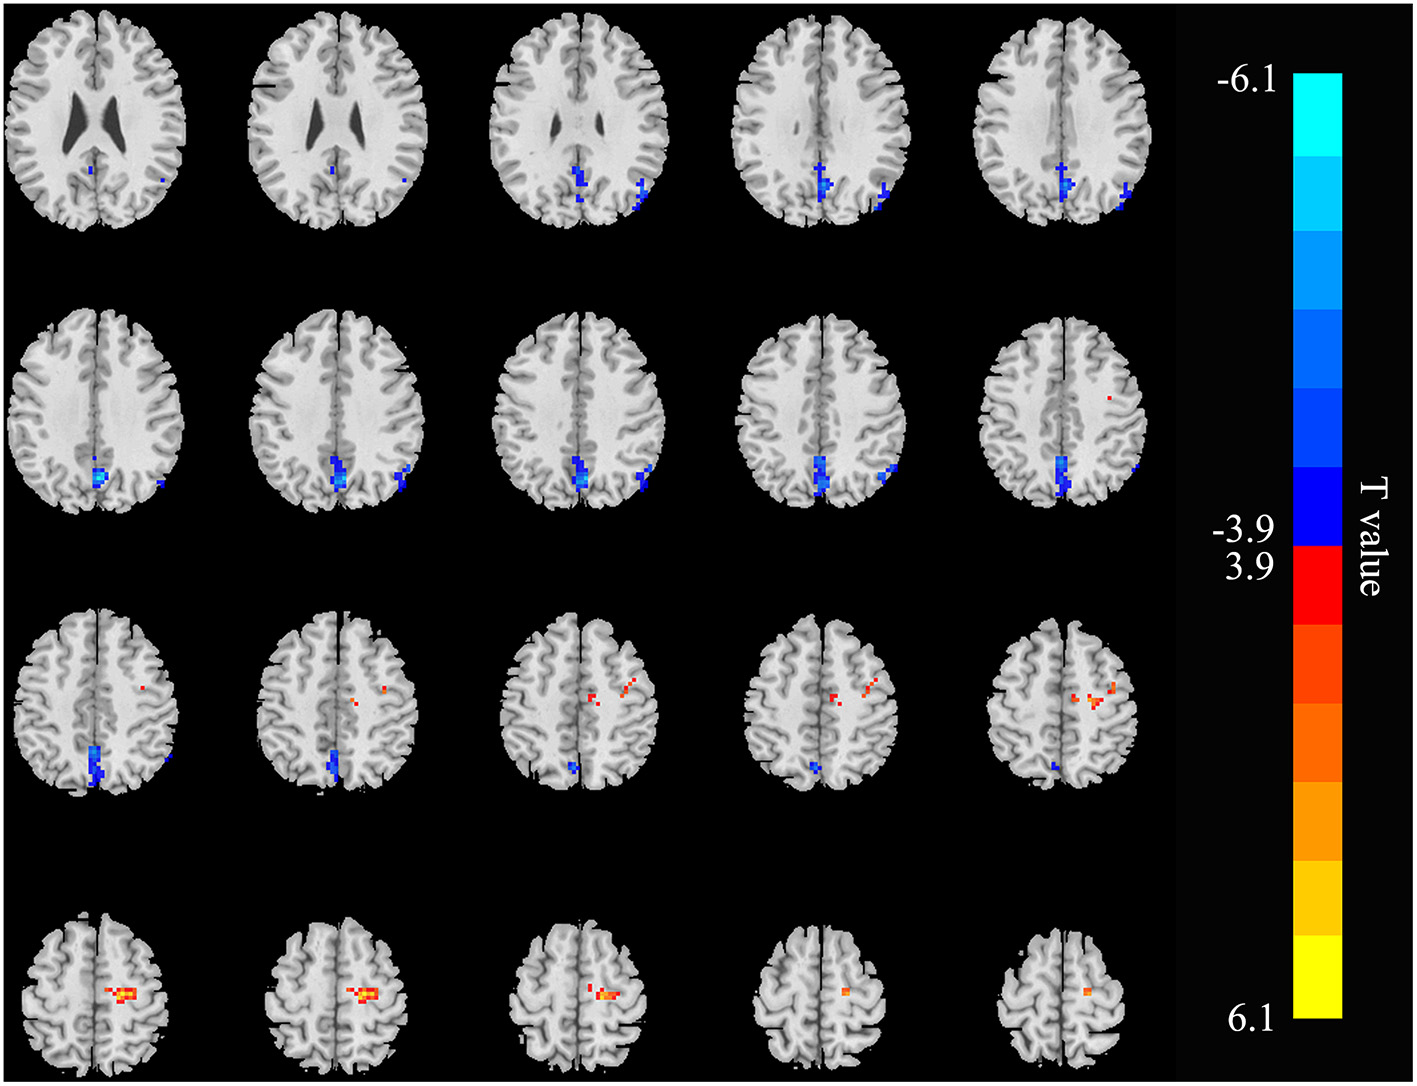

Relative to controls, the ALFF values of the right precuneus and angular gyrus (RAG) were significantly decreased in patients with ESRD. But the right precentral gyrus exhibited increased ALFF values in patients with ESRD compared with controls (Figure 1; Table 2). The ALFF values of the right precentral gyrus were negatively correlated with Hb (r = −0.487, p = 0.040, Figure 2), and the ALFF values of the right precuneus were negatively correlated with LTT results in patients with ESRD (r = −0.511, p = 0.036, Figure 3).

Figure 1

Brain areas showing ALFF differences in the patients with end-stage renal disease (ESRD) relative to controls (p < 0.05, FDR corrected). Patients with ESRD showed significantly decreased ALFF values in the right angular gyrus and precuneus. But the right precentral gyrus showed increased ALFF values in patients with compared with controls. ALFF, amplitude of low-frequency fluctuation; ESRD, end-stage renal disease. The color bar represents t-values, which is obtained by the two-sample t-test. The reduced ALFF value is represented by a cool color, while the increased ALFF value is expressed in warm color.

Table 2

| Brain areas | Voxel | Peak T score | MNI coordinates | ||

|---|---|---|---|---|---|

| x | y | z | |||

| Right angular gyrus | 51 | −4.8195 | 45 | −63 | 42 |

| Right precuneus | 162 | −6.0136 | 3 | −66 | 36 |

| Right precentral gyrus | 67 | 5.6244 | 21 | −18 | 57 |

Brain areas with different amplitude of low-frequency fluctuation (ALFF) values in the patients with end-stage renal disease (ESRD) relative to the controls.